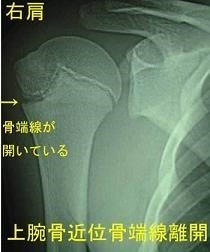

リトルリーグショルダーについて

リトルリーグ肩とは、野球肩とも言い、ピッチャーに最も多くみられる少年期の肩の障害の総称です。

・代表的な物として…

上腕骨近位骨端線離開(じょうわんこつきんいこったんせんりかい)があり、上腕骨(肩から肘までのいわゆる二の腕の骨)の肩の部分で、成長線と言われる部分がずれたり、離れたりするもので、骨折に準じた対応が必要です。

成長線は、骨端線(こったんせん)とも言い、骨が伸びるための軟骨組織で出来ています。

柔らかい軟骨組織が、固い骨組織に挟まれているため、ここでズレやすいのです。

成長線の部分の損傷ですので、後々成長障害を引き起こす可能性があります。